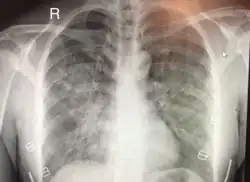

| Chest x-ray of HAPE showing characteristic patchy alveolar infiltrates with right middle lobe predominance. | |

On physical exam, increased breathing rates, increased heart rates, and a low-grade fever 38.5o C (101.3o F) are common.[9][3] Listening to the lungs may reveal crackles in one or both lungs, often starting in the right middle lobe.[9][3] Imaging studies such as X-ray and CT imaging of the chest may reveal thoracic infiltrates that can be seen as opaque patches.[14][9][3] One distinct feature of HAPE is that pulse oximetry saturation levels (SpO2) are often decreased from what would be expected for the altitude. People typically do not appear as ill as SpO2 and chest X-ray films would suggest.[9][3] Giving extra oxygen rapidly improves symptoms and SpO2 values; in the setting of infiltrative changes on chest X-ray, this is nearly pathognomonic for HAPE.[3]

Hypoxic pulmonary vasoconstriction (HPV) occurs diffusely, leading to arterial vasoconstriction in all areas of the lung. This is evidenced by the appearance of "diffuse," "fluffy," and "patchy" infiltrates described on imaging studies of climbers with known HAPE.[9]

The severity of HAPE is graded. The grades of mild, moderate, or severe HAPE are assigned based upon symptoms, clinical signs, and chest x-ray results for individuals.[8] The symptoms that are taken in to account while evaluation the severity of HAPE are difficulty breathing while exerting or while at rest, the presence of a cough and the quality of that cough, and the level of fatigue of the patient. On physical exam of a suspected HAPE patient the exam findings used to grade the severity are the heart rate, respiratory rate, signs of cyanosis, and severity of lung sounds.[8] Both symptoms and signs on physical exam can be used to evaluate a patient in the field. Chest X-rays are also used to evaluate the severity of HAPE when they are available.